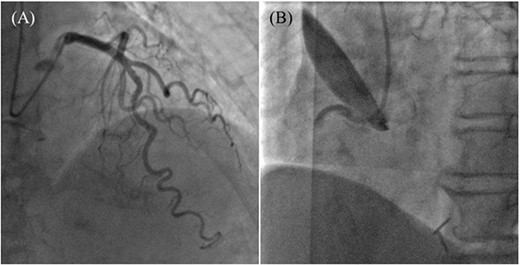

An 85-year-old woman with a history of hypertension and cerebral infarction presented to the emergency department of another hospital with the complaint of temporary loss of consciousness (LOC). Dehydration was suspected to be the cause of LOC; however, CAG was performed to confirm the reason for the mild elevation in creatine kinase and D-dimer levels. While the left coronary system was intact (Fig. 1A), the coronary dissection spread retrogradely from the right sinus of Valsalva to the ascending aorta after injecting contrast into the right coronary artery (RCA). The RCA was completely occluded at the proximal part, and no collateral flow into the RCA was observed (Fig. 1B). Electrocardiography revealed previously undetected ST elevation in leads II, III, and aVF and reciprocal ST depression in leads I, aVL, and V4–6 (Fig. 2). Contrast-enhanced CT confirmed aortic dissection which was localized in the ascending aorta (Fig. 3A). Additionally, RCA occlusion at the proximal portion was suspected (Fig. 3B). The patient was transferred to our institute for further management of the aortocoronary dissection. On arrival, the patient was alert and oriented with close to normal vital signs. Echocardiography showed a normal left ventricular ejection fraction with preserved RV function; however, severe hypokinesis of the inferior wall was noted. Moreover, as the hemodynamic status of the patient gradually deteriorated in the emergency department, we decided to perform an emergency surgery.

Coronary angiography images. (A) Intact left coronary artery without collateral blood supply into the right coronary artery (RCA). (B) Aortocoronary dissection of RCA with total occlusion.